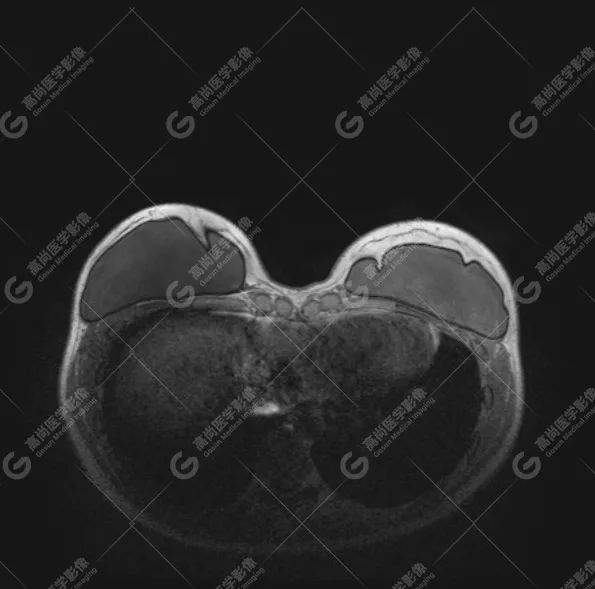

病例 1:乳腺假体植入术后 3 月余

双侧假体包膜光滑完整,内容物信号均匀。